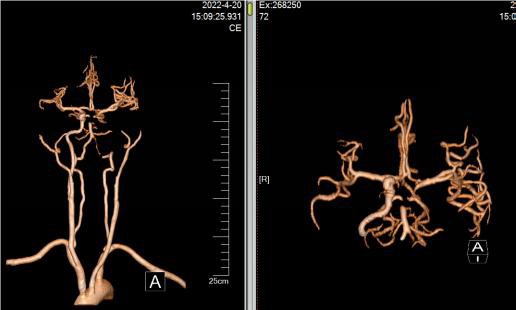

右侧颈总动脉造影

病历夹什么径技·第152期|串联营病历夹:川陕大营_https://www.jmylbn.com_新闻资讯_第46张

病历夹什么径技·第152期|串联营病历夹:川陕大营_https://www.jmylbn.com_新闻资讯_第47张

<<滑动查看下一张图片>>

• 出院时,患者意识清楚,精神可,夜休可,食纳可,大小便正常。

• 查体:生命体征平稳,心肺腹查体大致正常。神经系统查体基本同术前。(NIHSS评分1分)